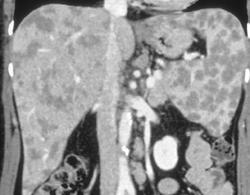

Splenic Laceration and Infarct